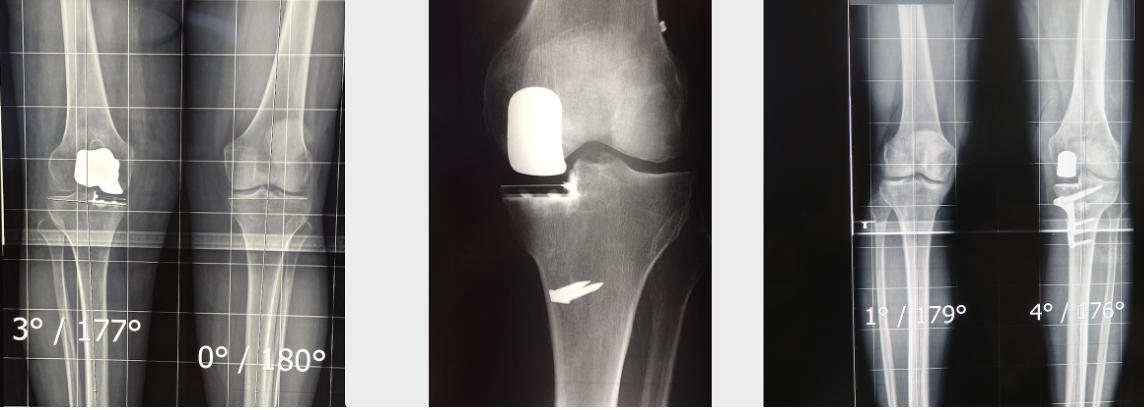

Poursuivant les travaux de ses illustres prédécesseurs, le Docteur Rouxel adhère au concept de chirurgie prothétique et conservatrice associant parfois d’autres gestes à la prothèse unicompartimentaire, le but final étant de supprimer la douleur liée à l’usure, de stabiliser le genou et de restaurer l’alignement du membre.

Ainsi sont apparues de nouvelles interventions combinant prothèse unicompartimentaire et reconstruction du ligament croisé antérieur, prothèse unicompartimentaire associée à une autre prothèse unicompartimentaire (remplaçant un autre compartiment malade sans utiliser une prothèse totale de genou) ou même prothèse unicompartimentaire et ostéotomie tibiale de réaxation en cas de déviation frontale importante.